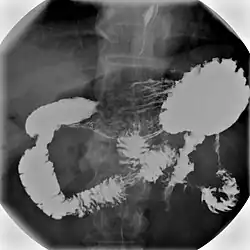

X-ray images are then taken in a supine position at intervals of 20–30 minutes. Real-time fluoroscopy is used to assess bowel motility. The radiologist may press or palpate the abdomen during images to separate intestinal loops. The total time necessary for the test depends on the speed of bowel motility or transit time and may vary between 1 and 3 hours.[17]